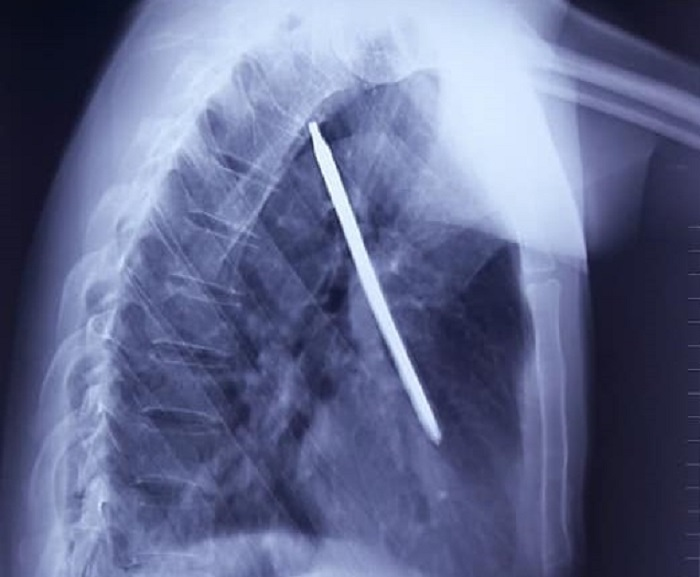

Hình ảnh chụp XQ cho thấy dị vật cắm sâu ở ngực trái của bệnh nhân.

Kết quả chụp X-quang cho thấy có dị vật trong lồng ngực. Bệnh nhân nhanh chóng được chuyển lên Khoa Ngoại tổng hợp để mổ cấp cứu, dẫn lưu màng phổi, lấy dị vật ra khỏi cơ thể.

Theo bác sỹ Hùng, dị vật là chiếc tuốc nơ vít đâm xuyên thành ngực trái, nằm trọn trong phổi sau, gần tim, có nguy cơ đe dọa tính mạng bệnh nhân nên các bác sĩ rất thận trọng khi phẫu thuật. Vật này văng lên đâm vào ngực anh N. khi anh đang cắt cỏ bằng máy.